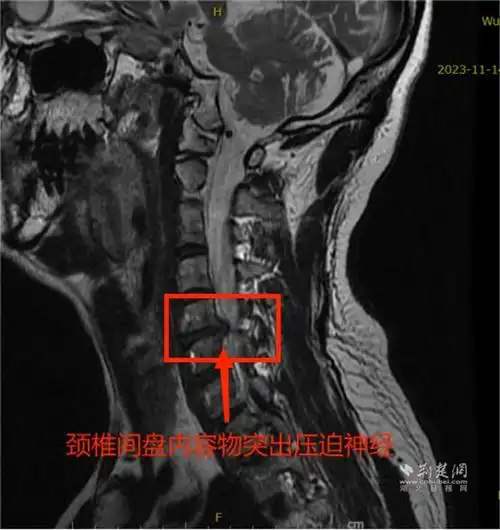

胳膊疼痛手麻乏力近两年病根儿竟是颈椎间盘突出